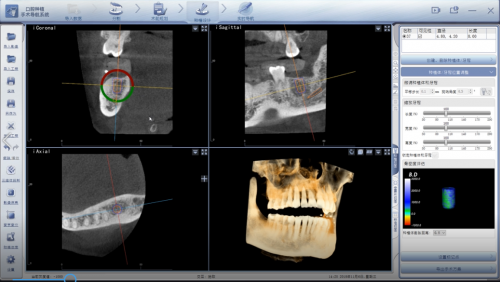

特别是近十年来,种植牙发展迅猛,在计算机辅助下的数字化技术,实现了手术的快速、精准、微创。其中口腔种植“动态导航”技术就是一种数字化全新升级的种植手段,它通过显示屏能够实时直观的看到种植体植入颌骨的全过程,全程监控种植位点、角度、深度,从而能有效避免损伤重要的解剖结构,降低手术风险,让手术更精准;对于牙齿缺失的患者来说,这一种植牙技术帮助他们实现当日手术、当日戴牙、当日进食的梦想的同时,缩短了愈合周期,减少患者诊疗次数,降低就医成本,能够让患者花更少钱,享受更一流的技术与服务。

(全程监控种植位点、角度、深度)